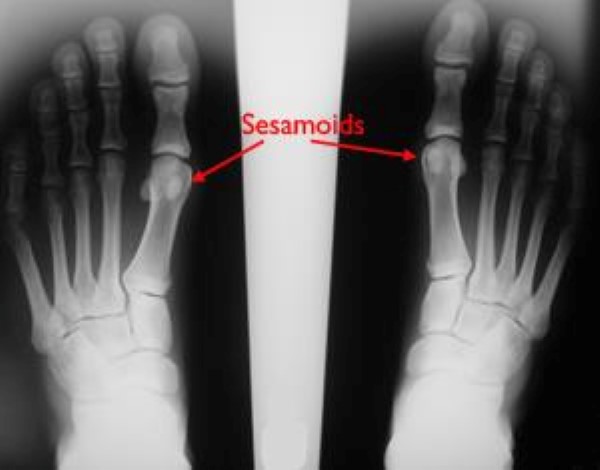

• Sesamoids. These two small bones are enveloped in the flexor hallucis tendon and help it to move more easily. In addition, the sesamoids provide stability to the MTP joint by helping to bear weight placed on the forefoot.

• X-rays. X-rays provide clear pictures of dense structures, like bone. Although the plantar complex is made up of different soft tissues, your doctor may order X-rays to make sure there are no other problems in your toe. These may include small bony pull-off fractures where the plantar complex attaches to the bones, and fractures or movement of the two small sesamoid bones.

The X-ray on the right shows normal bone positions. In the X-ray on the left, the sesamoid bones have moved into an abnormal position.